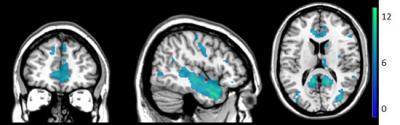

Researchers report that in three experiments involving 54 participants, significant distinctions emerged between self-touch and touch from others in neural processing at the cortical and spinal cord levels, with self-touch involving deactivation of several brain regions that were active during other-touch, as well as functional connectivity between the brain's sensorimotor cortex and insula and an elevated threshold for detection of additional tactile input.

Article #18-16278: "Distinction of self-produced touch and social touch at cortical and spinal cord levels," by Rebecca Böhme, Steven Hauser, Gregory Gerling, Markus Heilig, and Håkan Olausson.